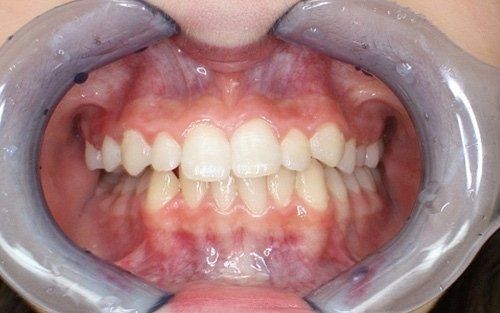

ORTODONZIA CLASSICA

Tramite brackets, ovvero attacchi (metallici, in resina o in ceramica) posizionati sui denti, viene realizzata una metodica fissa, con lo scopo di riallineare gli elementi dentari presenti in arcata raggiungendo la migliore occlusione possibile. L’opportunità di utilizzare una o l’altra tecnica, o una combinazione delle stesse dipende dalla diagnosi effettuata mediante le registrazioni iniziali.